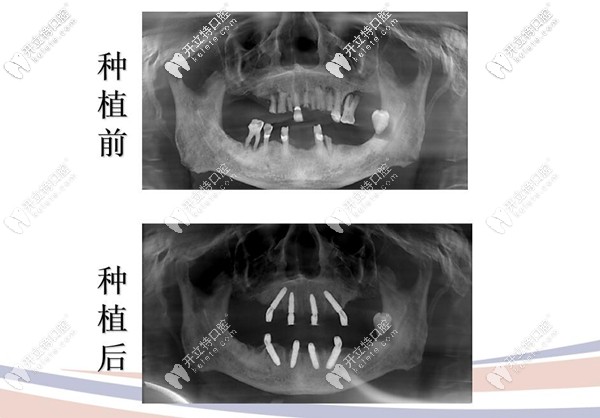

74歲的王叔,全口無牙且缺失多年,牙周炎三度,烤瓷牙松動,口腔狀況糟糕;

種植牙前后拍片圖示

治療方案:拔除松動牙,采用極光美式定制植牙All-on-4技術(shù),即刻種植,即刻修復(fù)當(dāng)天就能用哦!

顧客反饋:原來上下牙各用4顆種植體就可以恢復(fù)全口牙齒的咀嚼功能呀,這簡直有點(diǎn)神奇,當(dāng)天就可以吃東西,真的是錢花哪哪舒服啊,“我”也挺滿意的。